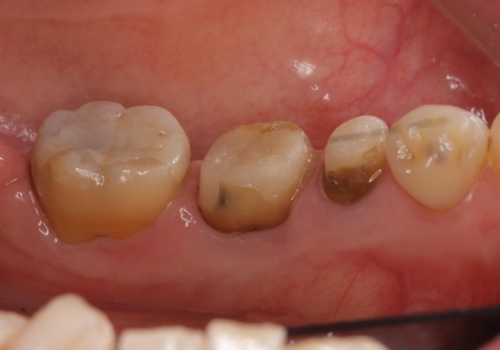

- 左下の銀歯を白くしたいと来院。

左下5番は根管治療のやりなおし、左下6番は上物(クラウン)のやり替えのみを行いました。

左下7番はアマルガムが入っていたため、ご希望によりセラミックインレーで治療を行っています。

- 44万円(内訳 左下7:emaxプレスインレー 左下6:仮歯、ジルコニアクラウン 左下5:精密根管治療再治療、ファイバーコア、仮歯、ジルコニアクラウン)費用は治療当時の料金となります